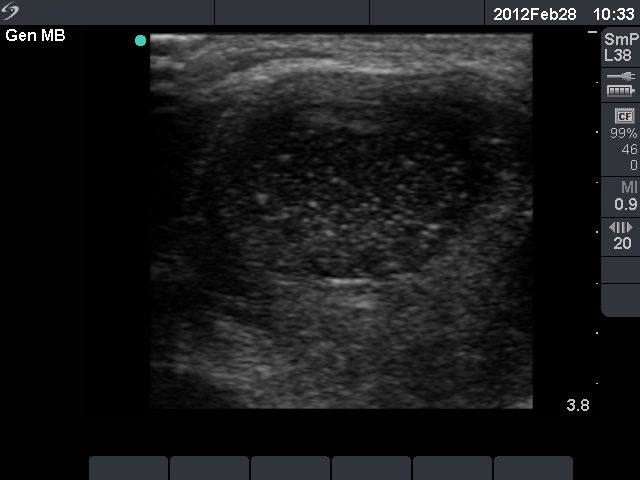

Third row: 3 days after the fourth session of ethanol treatment - the cyst became more enlarged and painful. The body temperature rose to 38.2 C, the erythrocyte sedimentation rate was 50 mm/H.

Ultrasonography: the size of the nodule was 30x25x34 mm, and another hyperechogenic lesion was found dorsal to the treated lesion.